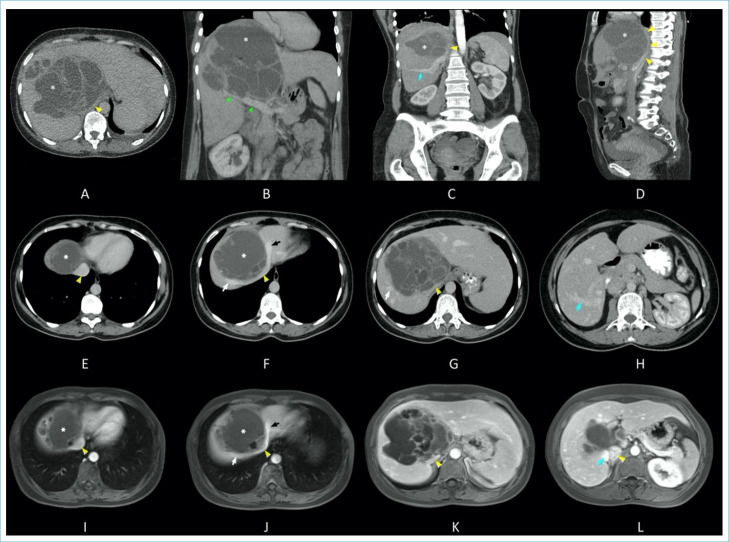

Biliary cystadenomas are uncommon lesions with clinical and radiological characteristics that overlap with other cystic liver lesions. Here, we intended to discuss a biliary cystadenoma found in a 37-year-old female patient who had been treated for a liver abscess and had been sent to our clinic with a long-term hydatid cyst diagnosis.

Abstract Image